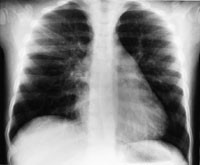

Røntgen thorax i serie med første bilde tatt to timer (fig 1) etter ekstubasjon viste fortetninger forenlig med interstitielt ødem og overlappsatelektase. Ødemet nærmest normaliserte seg i løpet av ni timer (fig 2) og fullstendig i løpet av 48 timer (fig 3), men med bestående atelektase. Pasienten var på dette tidspunkt helt ubesværet. Siste kontrollbilde tatt etter 14 dager var helt normalt.

Lungeødem som utvikles ved forsert inspirasjon har god prognose, men kan være assosiert med tilstander som i seg selv kan være livstruende. Det kliniske bildet varierer fra et fulminant lungeødem med blodtilblandet ekspektorat og klare røntgenfunn, til det mer vanlig forekommende moderate kliniske bildet med uklare røntgenfunn. Vår pasient hadde et moderat klinisk bilde, men røntgenbildene viste klare funn i form av en overlappsatelektase og interstitielt ødem (fig 1 – 3). All den tid pasienten var klinisk upåfallende før operasjonen og oksygeneringen var normal under operasjonen, tror vi lungeforandringene oppstod etter operasjonen. Overlappsatelektasen kan ha oppstått som en følge av det kraftige negative intrapleurale trykk under forsert inspirasjon, en trykkgradient som vil være maksimal mot lungetoppene hos en sittende eller stående pasient. Asymmetrien kan skyldes slimplugging. Derved er atelektasen et resultat av dynamisk lungekollaps som raskt reekspanderer spontant eller ved hjelp av CPAP-behandling. Tidlig bronchusavgang til høyre overlapp gjør denne sårbar for blokade av en tube som sitter like distalt for carina.